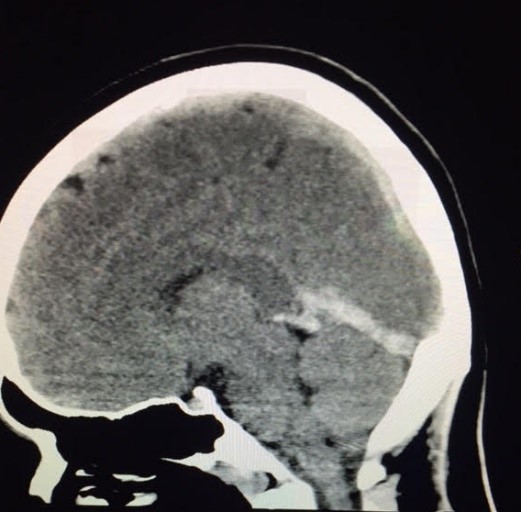

She was rushed to a regional medical center, where an initial CT scan of her head was concerning for blood around the brain. Sidney had already lost consciousness, leaving her family in a state of shock. They were informed that Sidney had a blood clot in her brain, and the future was uncertain. Because Sidney was unconscious, a breathing tube was placed, and after being connected to a ventilator she was transferred to Cleveland Clinic for more advanced care.

Sidney's journey led her to the Neurocritical Care Unit at Cleveland Clinic where her brain images were reviewed, revealing a cerebral venous sinus thrombosis—a significant blood clot throughout most of the venous structures in her brain. These clots were blocking blood flow out of her brain, causing elevated pressures that rendered her unconscious. Due to their severity, she was taken for a procedure to place a wire catheter into the veins of her brain to break up the clots. This would allow the blood to flow again and the pressure to normalize. But although the procedure was a success, Sidney’s journey was far from over.